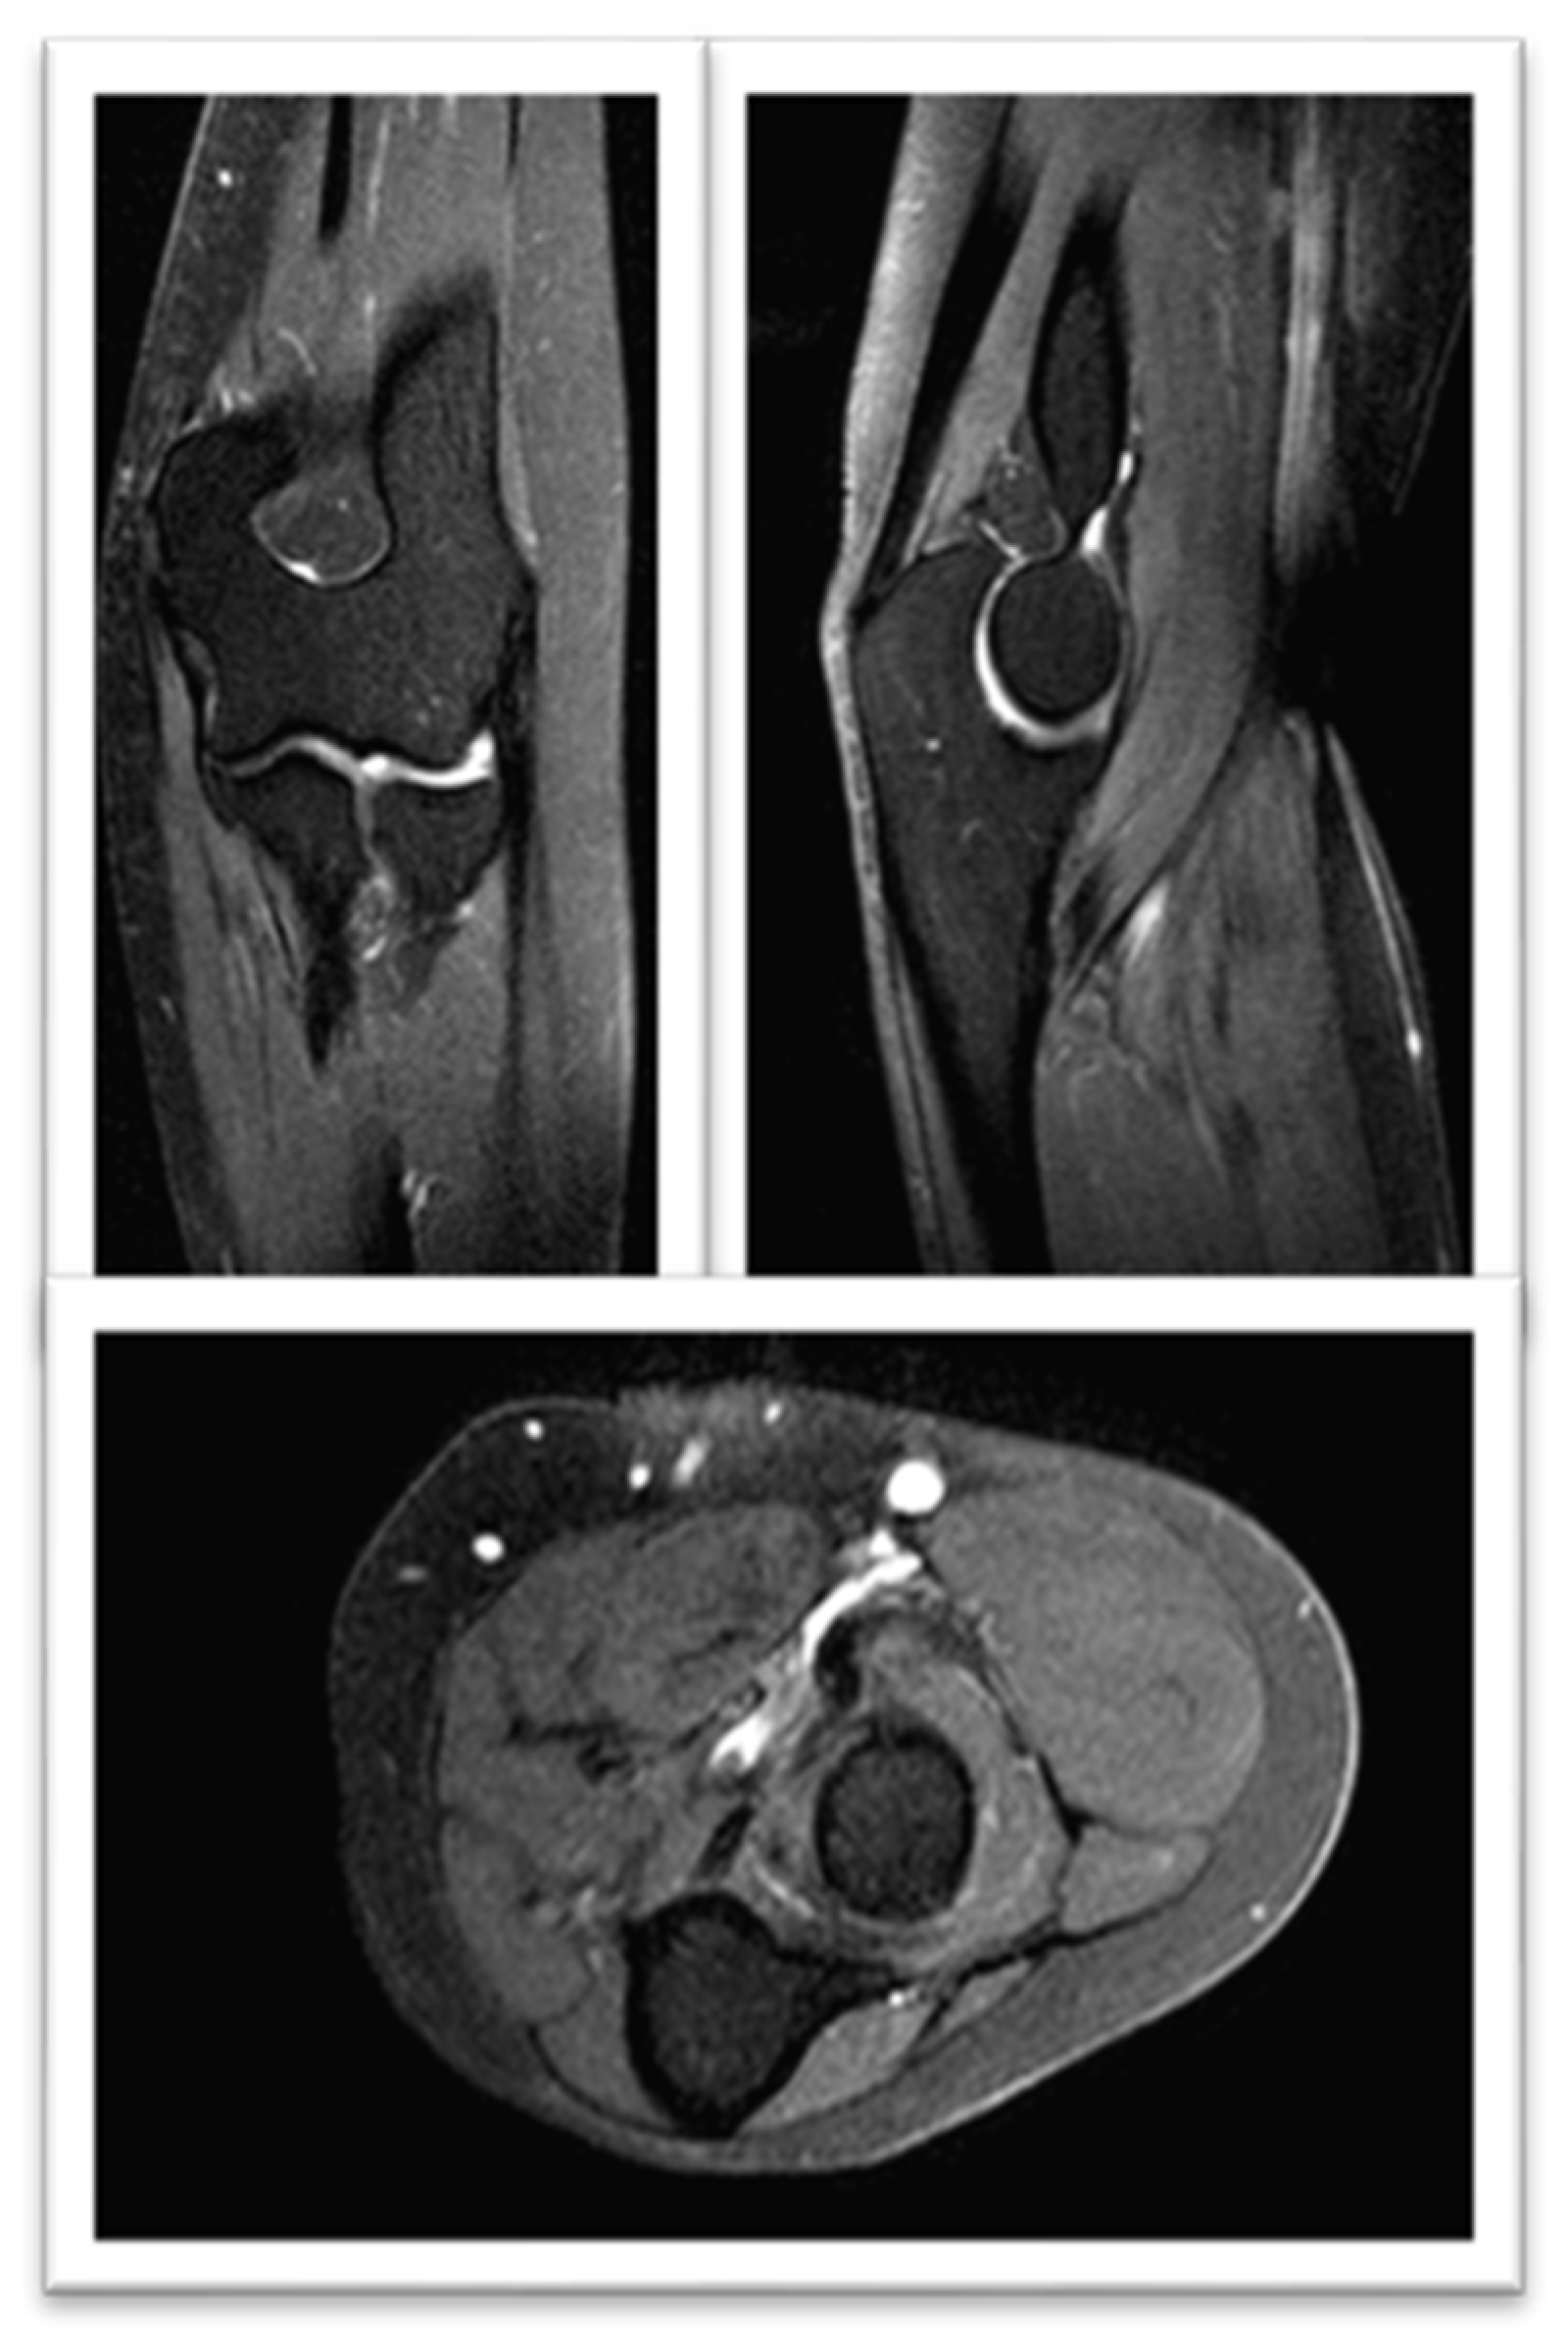

2. Case Report